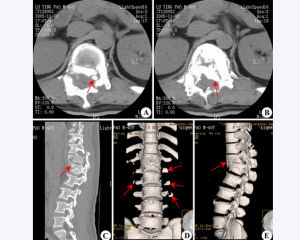

粉碎性骨折屬於完全性骨折,指骨質碎裂成三塊以上,又稱為T或Y型骨折。粉碎性骨

骨折分類及治療方法將骨折範圍在3cm內稱為一般粉碎性骨折,超過3cm者稱為嚴重粉碎性骨折。